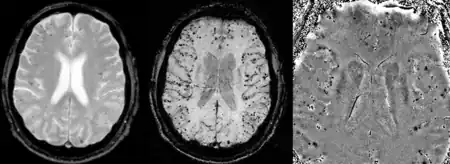

Images of CAA collected at 1.5 T. Left, conventional T2* (TE=20 ms), center, SWI processed magnitude image (TE=40 ms) and right, SWI phase image (TE=40 ms)

Gradient recalled echo (GRE) imaging is the conventional way to detect hemorrhage in CAA, however SWI is a much more sensitive technique that can reveal many micro-hemorrhages that are missed on GRE images.[7] A conventional gradient echo T2*-weighted image (left, TE=20 ms) shows some low-signal foci associated with CAA. On the other hand, an SWI image (center, with a resolution of 0.5 mm x 0.5 mm x 2.0 mm, projected over 8mm) shows many more associated low-signal foci. Phase images were used to enhance the effect of the local hemosiderin build-up. An example phase image (right) with yet higher resolution of 0.25 mm x 0.25 mm x 2.0 mm shows a clear ability to localize multiple CAA-associated foci.